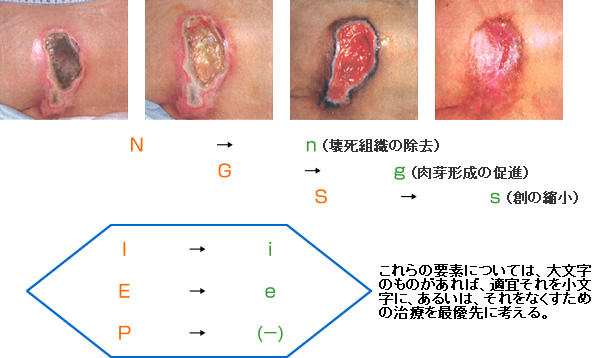

褥瘡の「創縁」「創面」の性状を把握しよう 2ページ目 :日経DI。

慢性期褥瘡の局所治療局所治療の概要褥瘡辞典 for MEDICAL PROFESSIONAL医療関係者向け情報マルホ株式会社。

トラブル&ケア日常のトラブル過剰肉芽の物理的切除NPO法人PDN。

⑤深い褥瘡攻略の道標 ”TIME+α”のE 創部辺縁の段差 :難関攻略!褥瘡ポケットを治す秘策とは!? -皮膚科専門医が伝授!医療従事者のための高齢者皮膚トラブル対策講座。